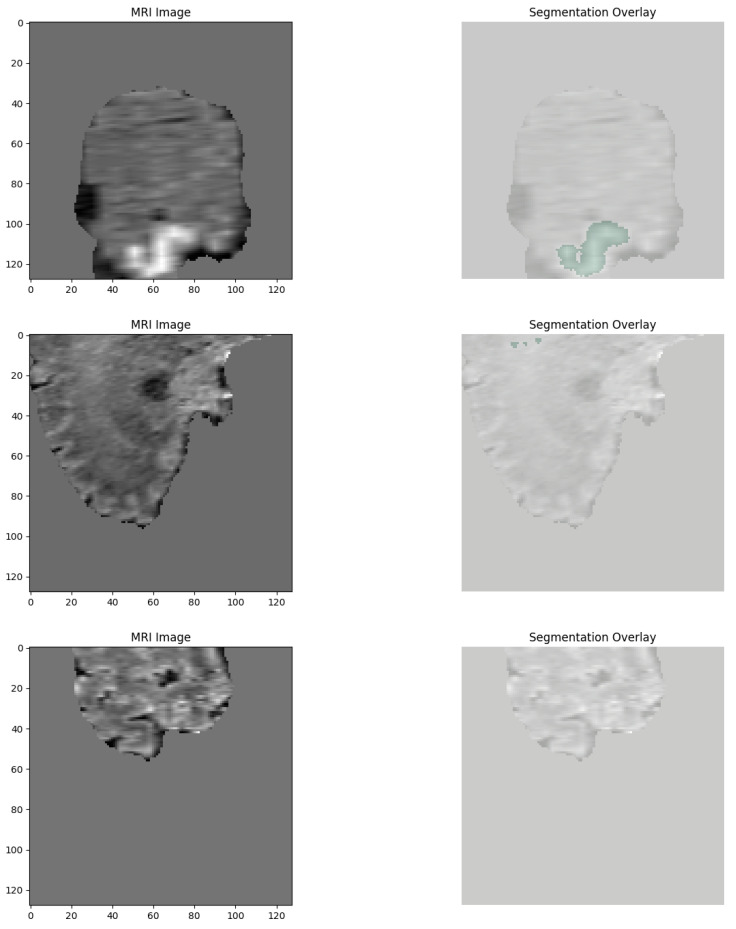

Methods: A diagnosis system was developed combining 2D tumor classification and 3D volumetric segmentation. Classification employed a fine-tuned MobileNetV2 model trained on a glioma, meningioma, pituitary tumor, and normal control dataset. Segmentation employed a SegResNet model trained on BraTS multi-channel MRI with synthetic no-tumor data. A meta-classifier MLP was used for binary tumor detection from volumetric features. Explainability was offered using XRAI maps for 2D predictions and Gaussian overlays for 3D visualizations. The platform was incorporated into a web interface for clinical use.

Results: MobileNetV2 2D model recorded 98.09% classification accuracy for tumor classification. 3D SegResNet obtained Dice coefficients around 68-70% for tumor segmentations. The MLP-based tumor detection module recorded 100% detection accuracy. Explainability modules could identify the area of the tumor, and saliency and overlay maps were consistent with real pathological features in both 2D and 3D.